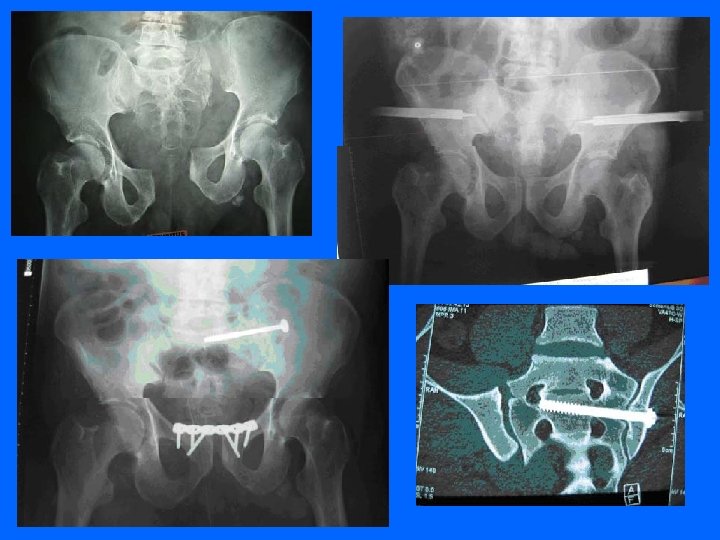

Radiographie La radiographie du bassin de face est

Radiographie La radiographie du bassin de face est systématique devant tout polytraumatisé • les incidences du bassin ascendante et descendante.

les incidences de ¾ de la hanche pour dégager le cotyle

scanner Apporte des renseignements sur l'état des structures postérieures

Trt Chirurgical L'ostéosynthèse : obtenir une réduction anatomique et une stabilité immédiate, qui évite un alitement prolongé. Ostéosynthèse par plaques vissées sur la symphyse pubienne ou par vis ilio-sacrées.

Fixateur externe : stabilise rapidement et sans ouvrir les disjonctions antérieures et postérieures. permet de traiter tout de suite les lésions associées